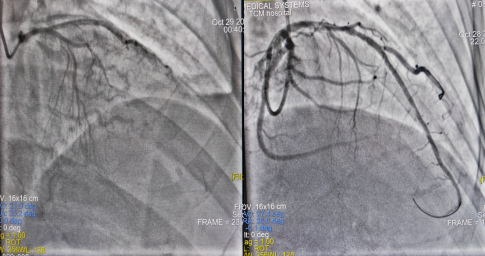

10月28日17:37分,65岁的刘先生,因腹泻数天伴胸闷胸痛前往当地医院,心电图提示下壁ST段抬高,考虑急性心肌梗死,由120护送至我院,病程中患者心率最慢只有34次/分,立刻启动导管室,绕行急诊科、CCU,直达导管室,为患者进行临时起搏器植入+急诊CAG+冠脉内溶栓+PTCA术,术后患者生命体征平稳,转危为安。

图1术前造影结果图2 球囊扩张图3治疗后造影